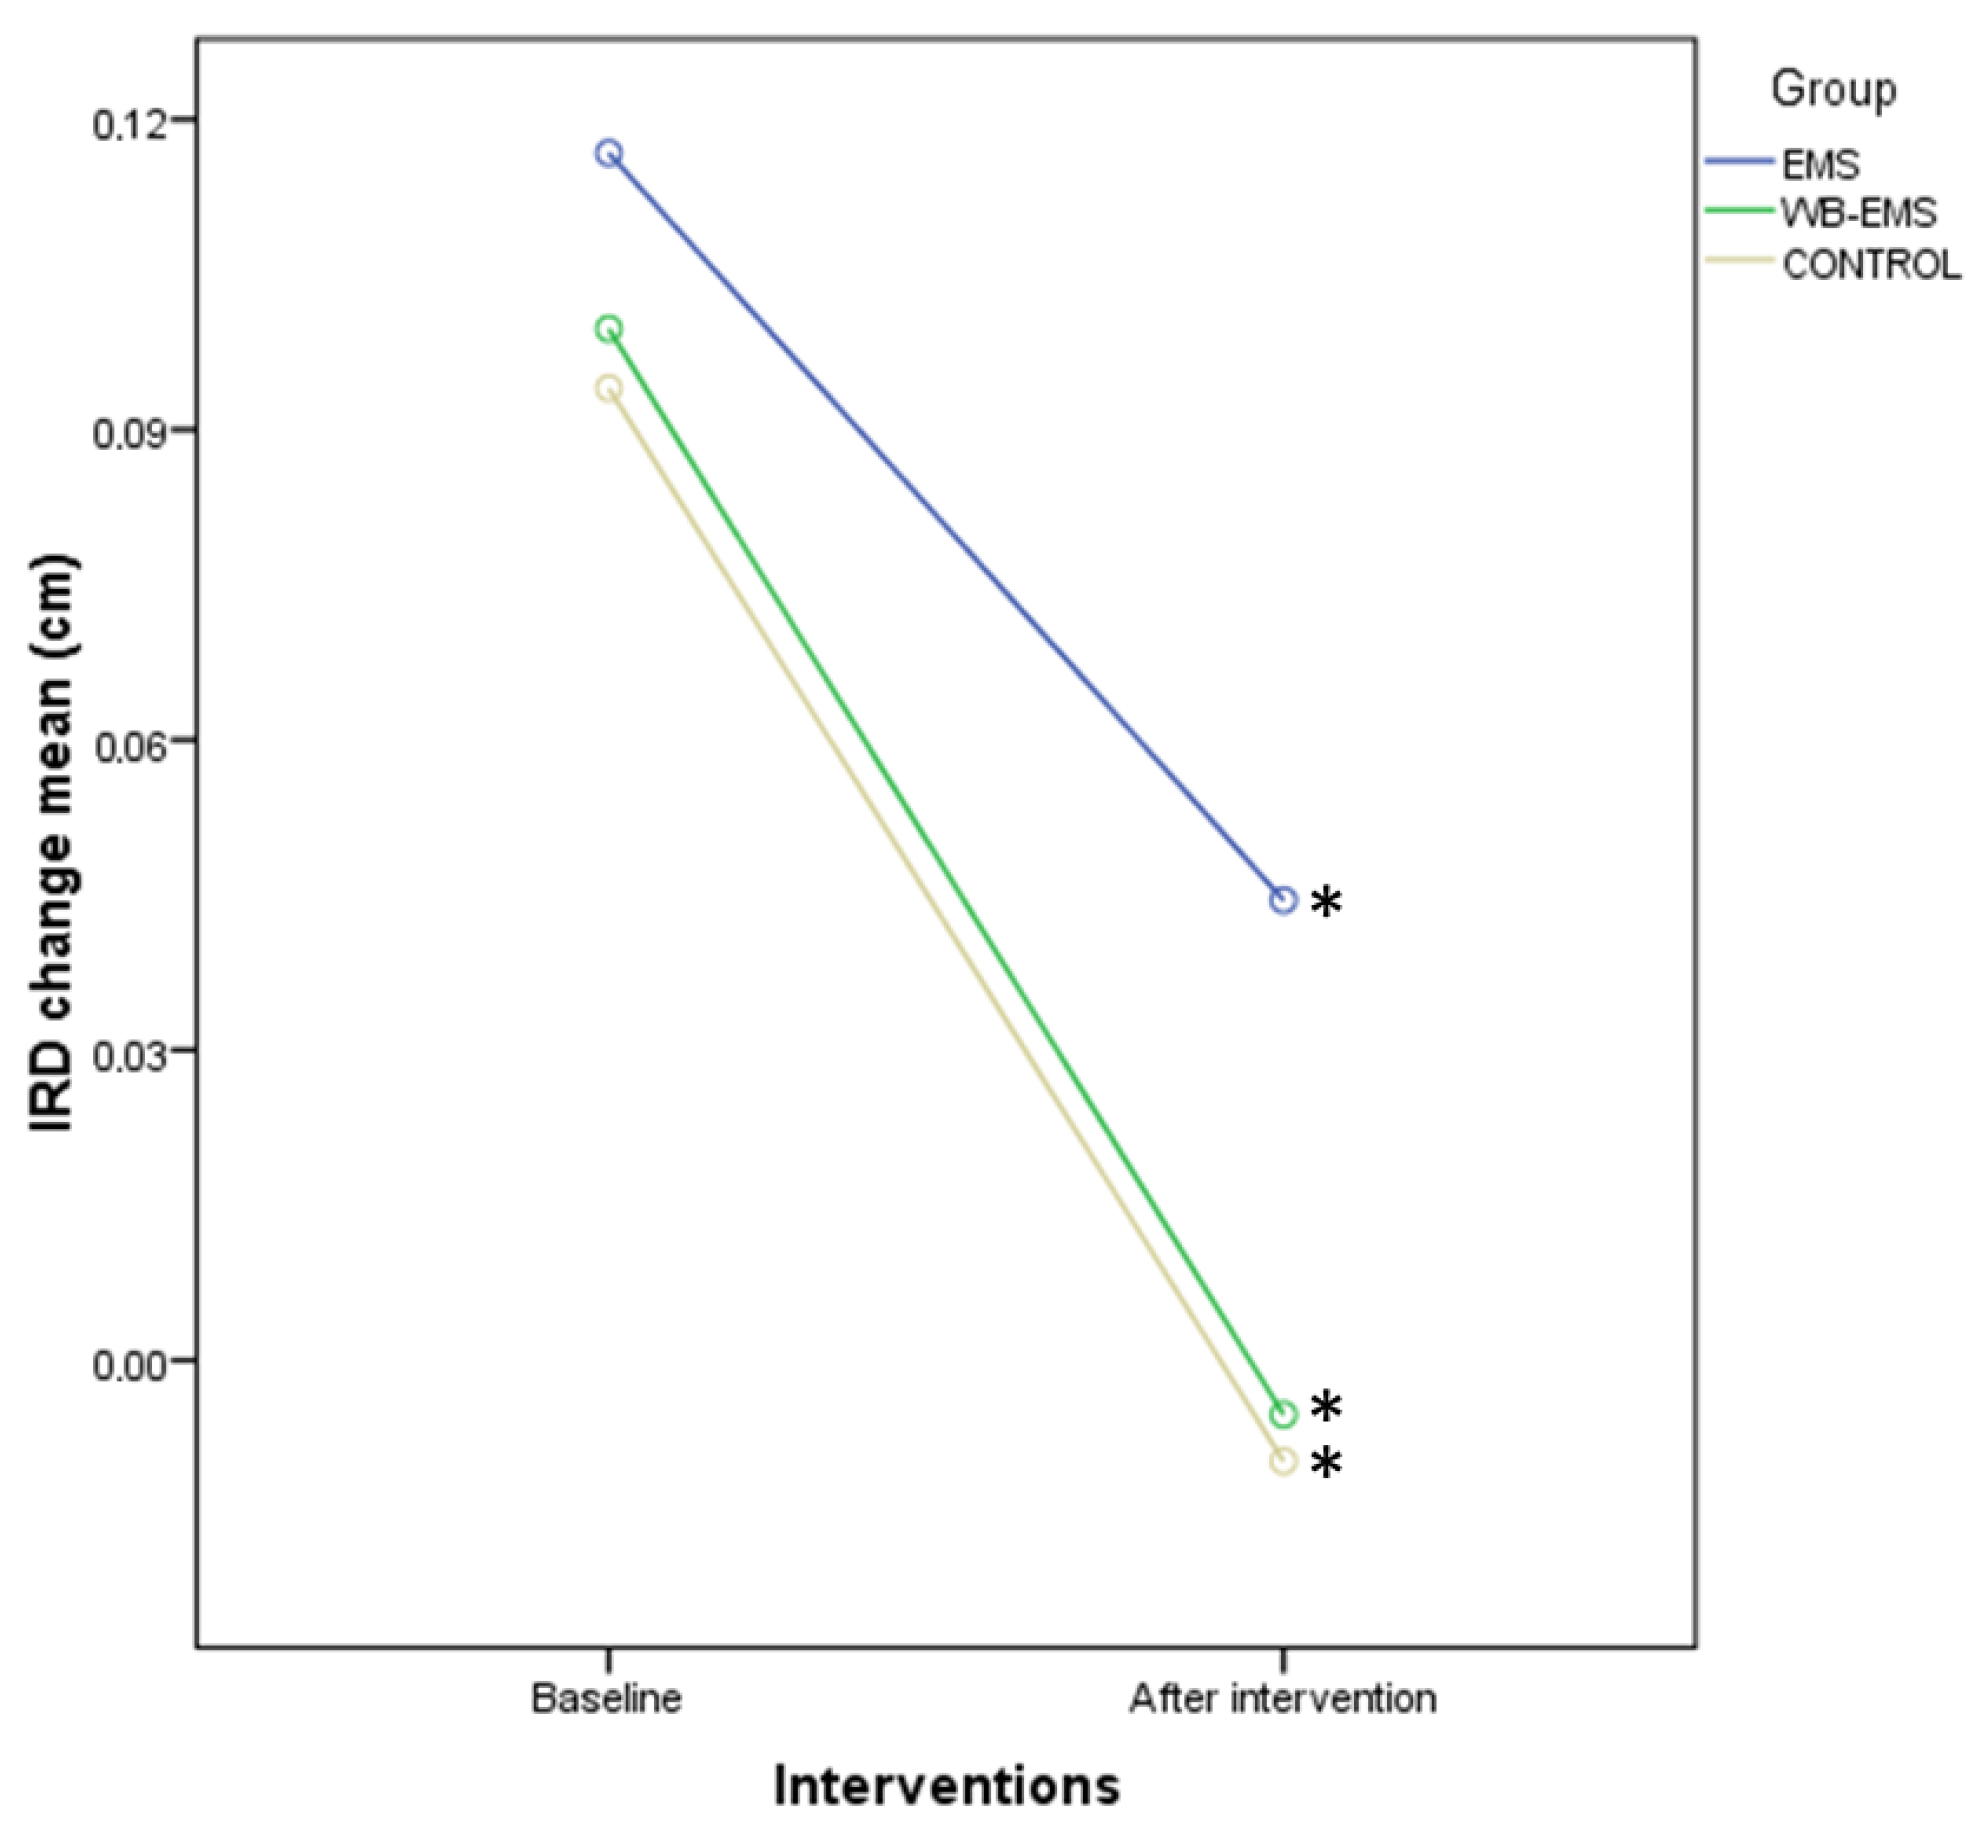

3.3. Outcome Measurements Differences after Interventions

3.4. Two-Way ANOVA of Repeated Measurements for Intra- and Intergroup Comparisons

| IRD change (cm) | 0.09 ± 0.23 (−0.20–0.61) | 0.08 ± 0.11 (−0.19–1.03) | 0.09 ± 0.09 (−0.12–0.38) | 0.715 † |

| IRD change (cm) | 0.09 ± 0.23 (−0.20–0.61) | 0.03 ± 0.23 (−0.35–0.45) | −0.07 ± 0.18 (−0.58–0.22) | 0.08 ± 0.11 (−0.19–1.03) | −0.01 ± 0.15 (−0.22–0.33) | −0.07 ± 0.18 (−1.09–0.18) | 0.09 ± 0.09 (−0.12–0.38) | 0.03 ± 0.08 (−0.09–0.15) | −0.09 ± 0.18 (−0.46–0.22) | 0.597 † |